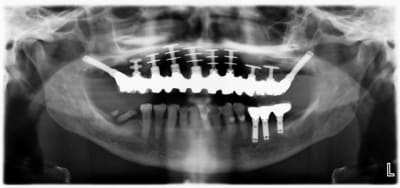

il y a des péri-implantites sur quasi tout les disk du haut, c'est cà?

Fabuleuses ces pano avec des diskimplants, ça defit notre mode de pensée implantaire actuel. En tout celui qui a traité ce patient n'était pas un manchot.

En pratique, c'est quoi le problème avec les disk ? On voit pas bien sur la pano periimplantite ? sinon il va y avoir besoin d'encore un peu de titane en secteur 4

et un si grand nombre de disques et 2 implants ptérygoidiens bien posés je ne vois que lui

et je ne vois pas comment ça pourrait bouger : les implants ptérygoidiens sont bien integres

ça aussi c'est fait par le grand Maître, je garderai mon avis pour moi parce que je n'ai pas compris le rationnel pour faire ça à une patiente...

C'est quand même d'un point de vue technique sacrément impressionant...

oui mais autour de cette radio il y a une patiente qui doit vivre, maintenir et avoir mal après cette prouesse technique. je préfère un truc simple qui marche à une prouesse technique qui merde

Non, ce n'est pas un problème de tourne disque mais plutôt de peri-implantite dans le secteur antérieur.

Effectivement, pas de mobilité.